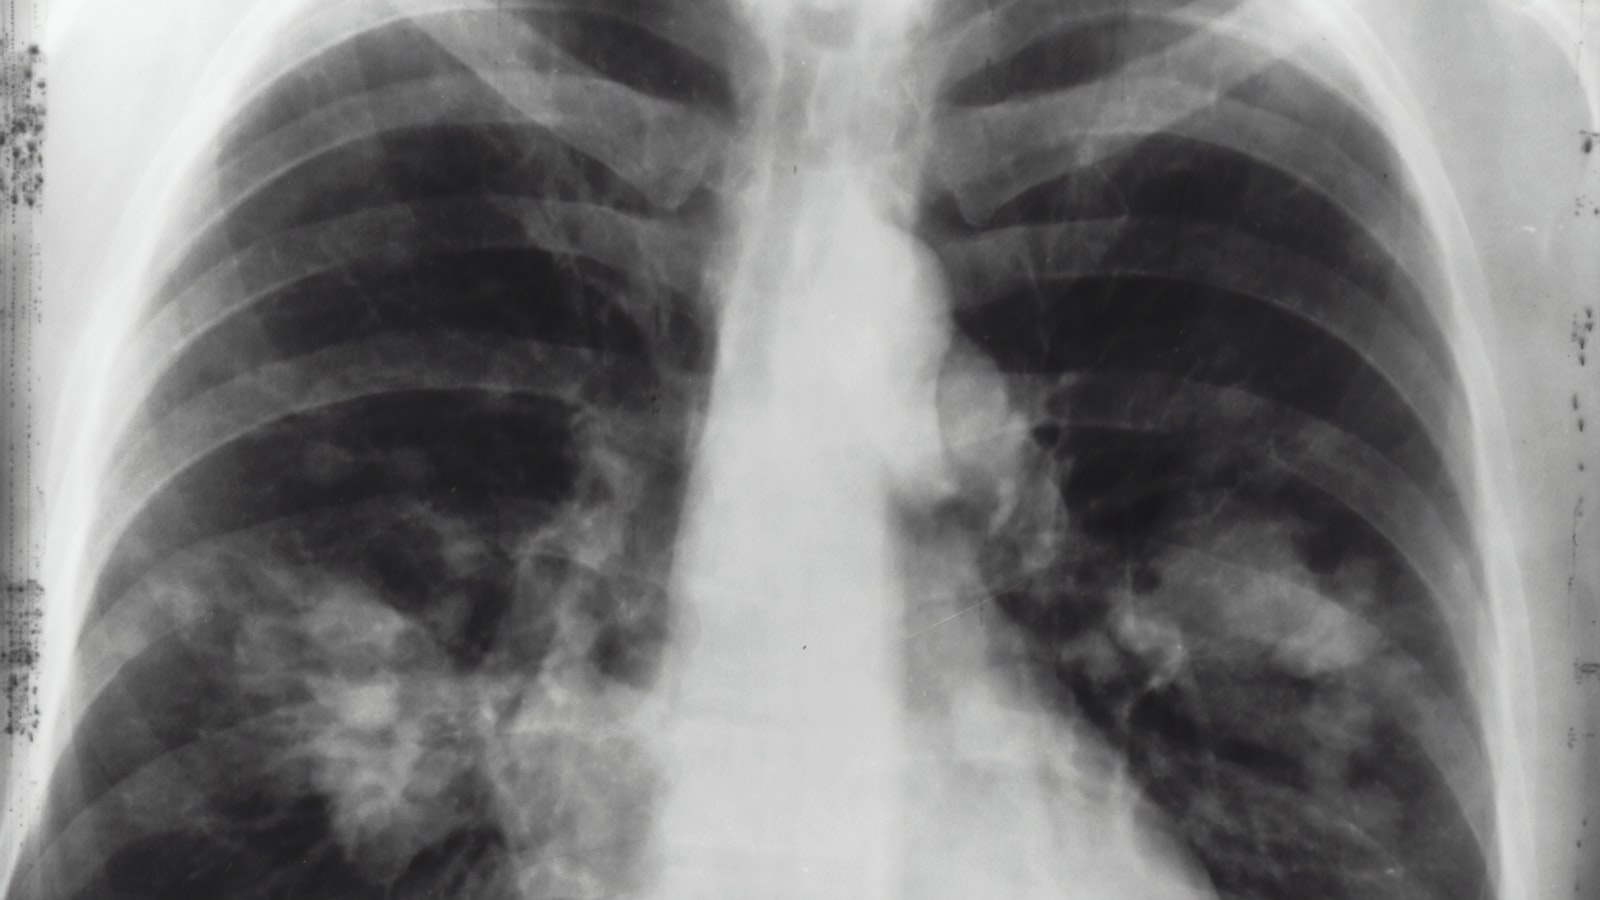

또한 진단에는 폐 전산화 단층촬영(CT)이 사용될 수도 있습니다. 폐 CT는 폐의 구조와 기능에 대한 더 상세한 정보를 제공하며, 폐 질환과 연관된 다른 이상 소견을 확인하는 데 도움을 줍니다. 환자의 기침이나 가래, 폐기능 검사 결과에 따라 의사는 폐 CT를 권장할 수 있습니다.